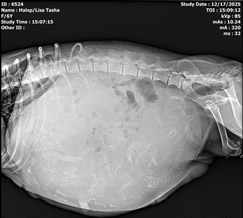

Tasha was very kind to me and decided to have her litter during the DAYTIME, on a WEEKDAY! Seven puppies and we were done! Four boys and three girls; all tri-colored and all huge and thriving. Tasha is tired but as always a great mom and is taking wonderful care of her babies. The ultrasound pic shows one pup and it's beating heart in Nov, and looking at the x-ray, can you make out the babies in her abdomen before they were born? We count skulls and spines - that's how I know how many to expect.